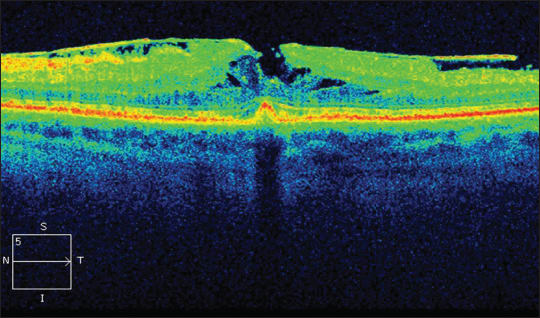

Optical coherence tomography has revolutionized our ability to visualize and examine the vitreomacular interface. This evolution has not only allowed clinicians to differentiate between the various pathologies more accurately, but it has also led to a better appreciation of the processes that are involved in creating these conditions. In turn, there has been a change in the paradigm of viewing the pathologies as separate entities toward recognition that they are all part of a spectrum, sharing the same pathological processes (Figures 7, 8, and 9).

Figure 8. SD-OCT demonstrating MPH (ERM and steepened foveal contour), but with reduced foveal retinal thickness more commonly associated with LMH.